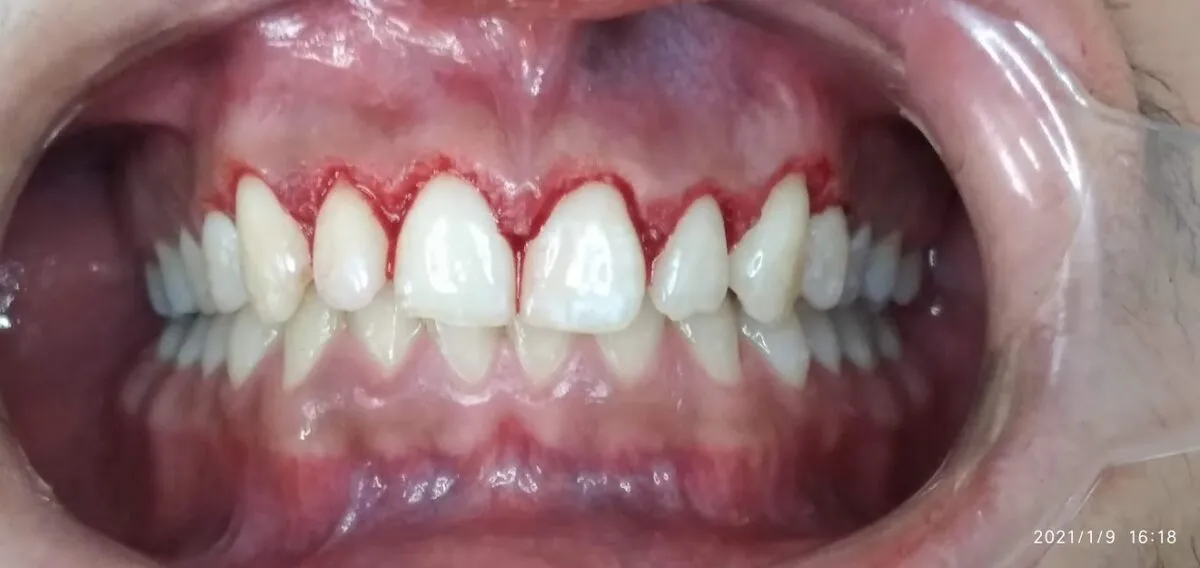

In this article we will show you a case of gingivectomy from before, during and after